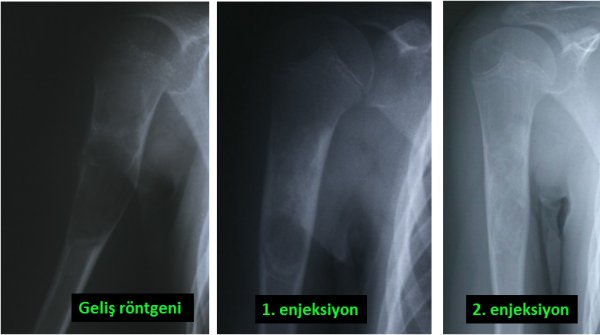

İyi huylu kemik tümörleri ise daha çok kemik kistleri, kıkırdak kökenli bazı tümörler yada dev hücreli kemik tümörü gibi bir takım lezyonlardır. Kistler basit olabileceği gibi kompleks de olabilir. Basit kemik kistleri daha çok çocuklarda görülür. En sık bölge omuz çevresi olmakla beraber her kemikte ortaya çıkabilir (resim-5). Basit kemik kistinin tedavisinde bazı durumlarda ameliyat gerekirken bazen de ameliyatsız tedavi uygulanabilir. Bunun için hastaya ameliyathane şartlarında kist içine enjeksiyon uygulanır ve bunu birkaç kez tekrarlamak gerekebilir (resim-6). Kompleks kist ile anlatılmak istenen ise “anevrizmal” kemik kistidir. Bunun tedavisi sadece cerrahi olup kist temizlendikten sonra içi bir takım özel maddelerle muamele edilmelidir. Oluşan boşluk kemik çimentosu yada kemik tozlarıyla doldurulur (resim-7). Anevrizmal kemik kisti basit kemik kistine göre daha saldırgan bir lezyon olup bazen kemiği tamamen ortadan kaldırabilir. Bunda nüks olasılığı da daha fazladır.